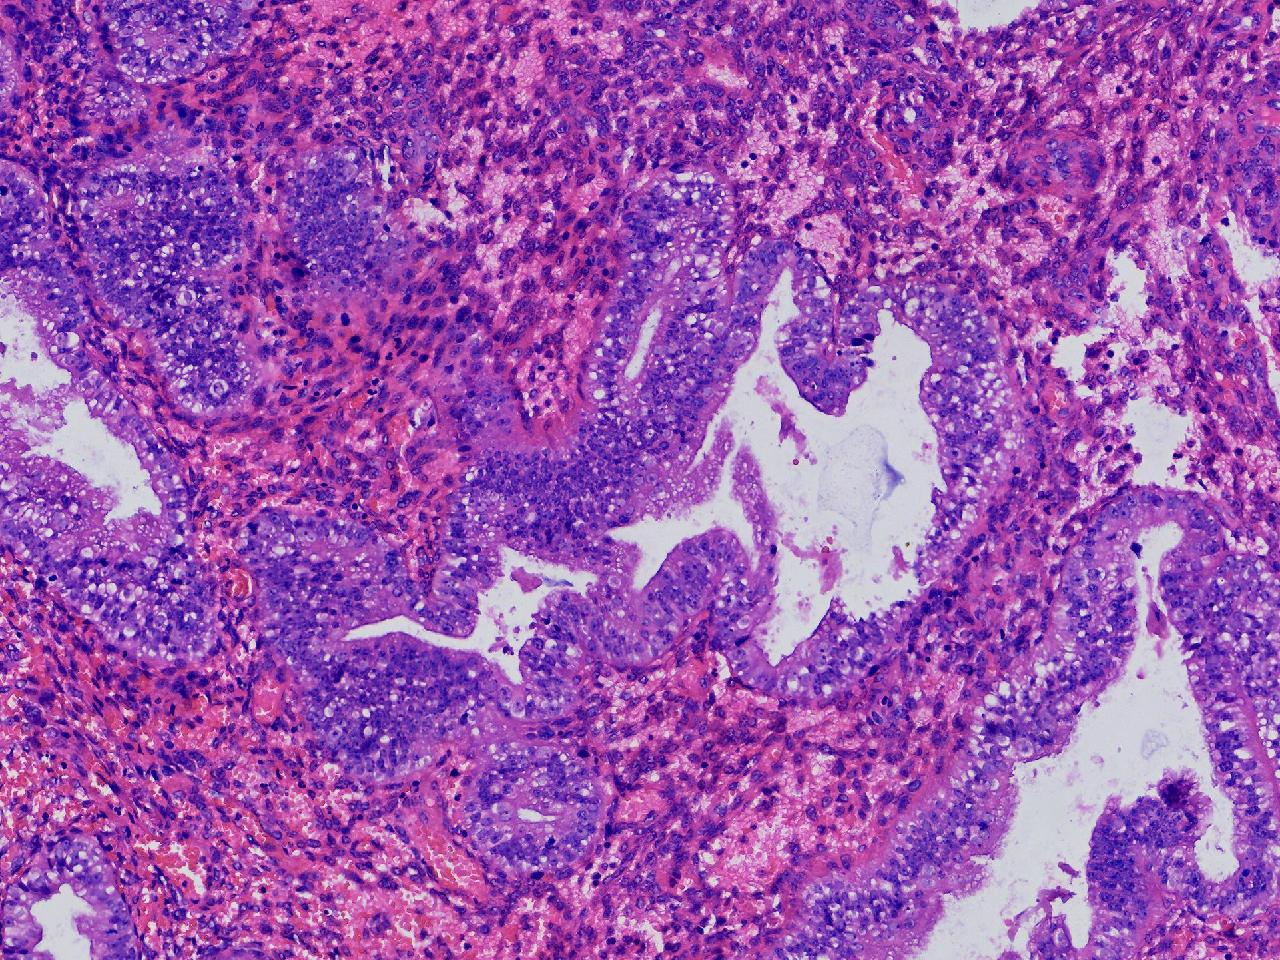

请教诊断.有没有非典?

女,50岁,彩超示:内膜厚1.3cm。

子宫内膜

灰粉色不整形软组织多块,2X2X1厘米。

无非典型性子宫内膜增生

无非典。